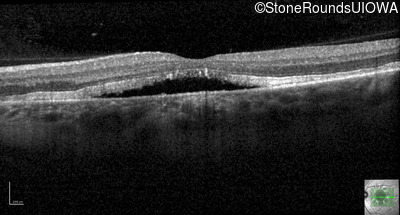

Optical Coherence Tomography - Left - 20/25 +2

Exemplar / OCT Stack

OCT Stack